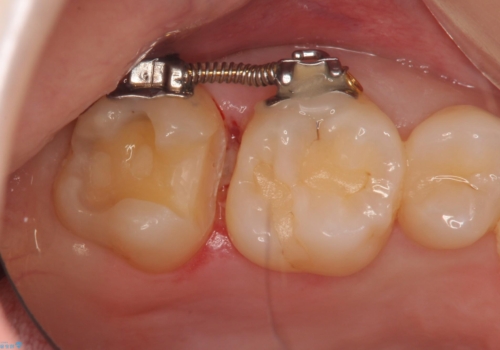

そこで、部分矯正を行い、歯の間を広げてしっかりした歯型を取りました。

広げた期間は2週間ほどです。

広げた後は歯が接するように修復するため、物が詰まることはありません。